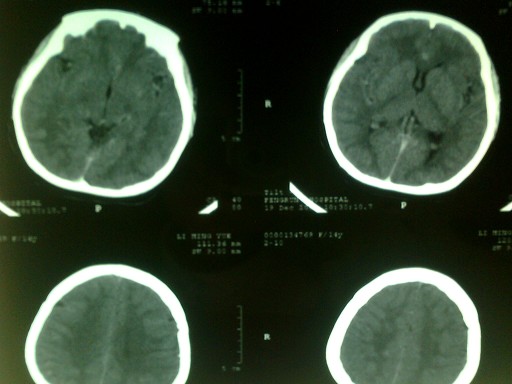

以下是引用dyqct在2008-12-20 16:16:00的发言:[br]查一下血红蛋白。长期缺氧引起血蛋白明显升高,可造成血管内血液密度增高。